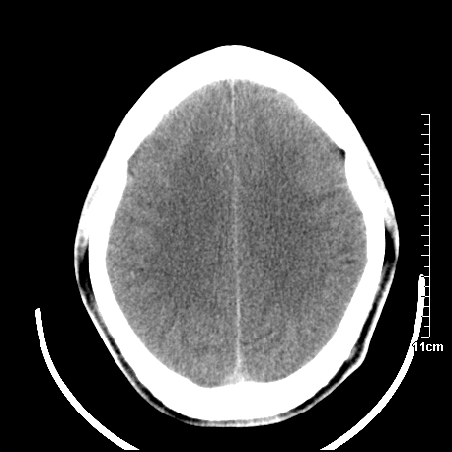

头晕.头痛间断意识恍惚1周 m/21y

4天上述症状加重伴左侧肢体发软,复查ct,

3.右侧颞叶低密度区考虑脑血管畸形

右側额叶、放射冠区灰白质改变,建议ct增强或mri检查

右侧放射冠区混杂密度灶,边缘不清,病人较年轻,结合有发热病史,支持感染性病变,建议密切结合临床可抗感染治疗后复查。

右侧颞叶病变定性困难,既然发病急,又有发热,脑脓肿不能除外。

右侧颞叶混杂密度灶,强烈建议:增强ct检查